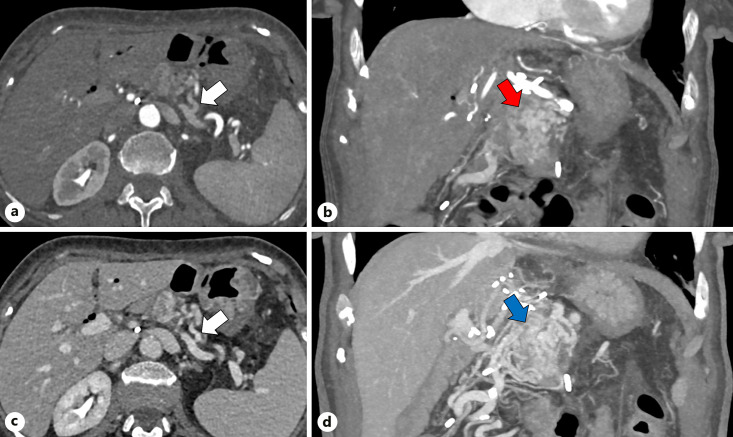

Background: Sinistral, or left-sided, portal hypertension (SPH) is a rare cause of upper gastrointestinal (GI) hemorrhage resulting from obstruction of the splenic vein. Venous drainage from the spleen via collaterals can result in venous hemorrhage into both the retroperitoneal and intra-abdominal spaces due to increased venous blood pressure in peripancreatic and gastroduodenal vasculature. SPH can occur secondary to pancreatitis with thrombosis of the splenic vein. Another possible cause is the surgical ligation of the splenic vein as part of pancreaticoduodenectomy (PD). Although splenectomy has been traditionally considered as the treatment of choice to relieve venous hypertension, individual concepts for each patient have to be developed. Considering the venous collateral drainage pathways, a comprehensive approach involving surgical, endoscopic, and interventional radiology interventions may be necessary to address the underlying cause of variceal bleeding. Among these approaches, splenic artery embolization (SAE) has demonstrated efficacy in mitigating the adverse effects associated with elevated venous outflow pressure.

Summary: This review summarizes key imaging findings in SPH patients after PD and highlights the potential of minimally invasive embolization for curative treatment of variceal hemorrhage.

Key messages: (i) SPH is a potential consequence after major pancreas surgery. (ii) Collateral flow can lead to life-threatening abdominal bleeding. (iii) Depending on the origin and localization of the bleeding, a dedicated management is required, frequently involving interventional radiology techniques.